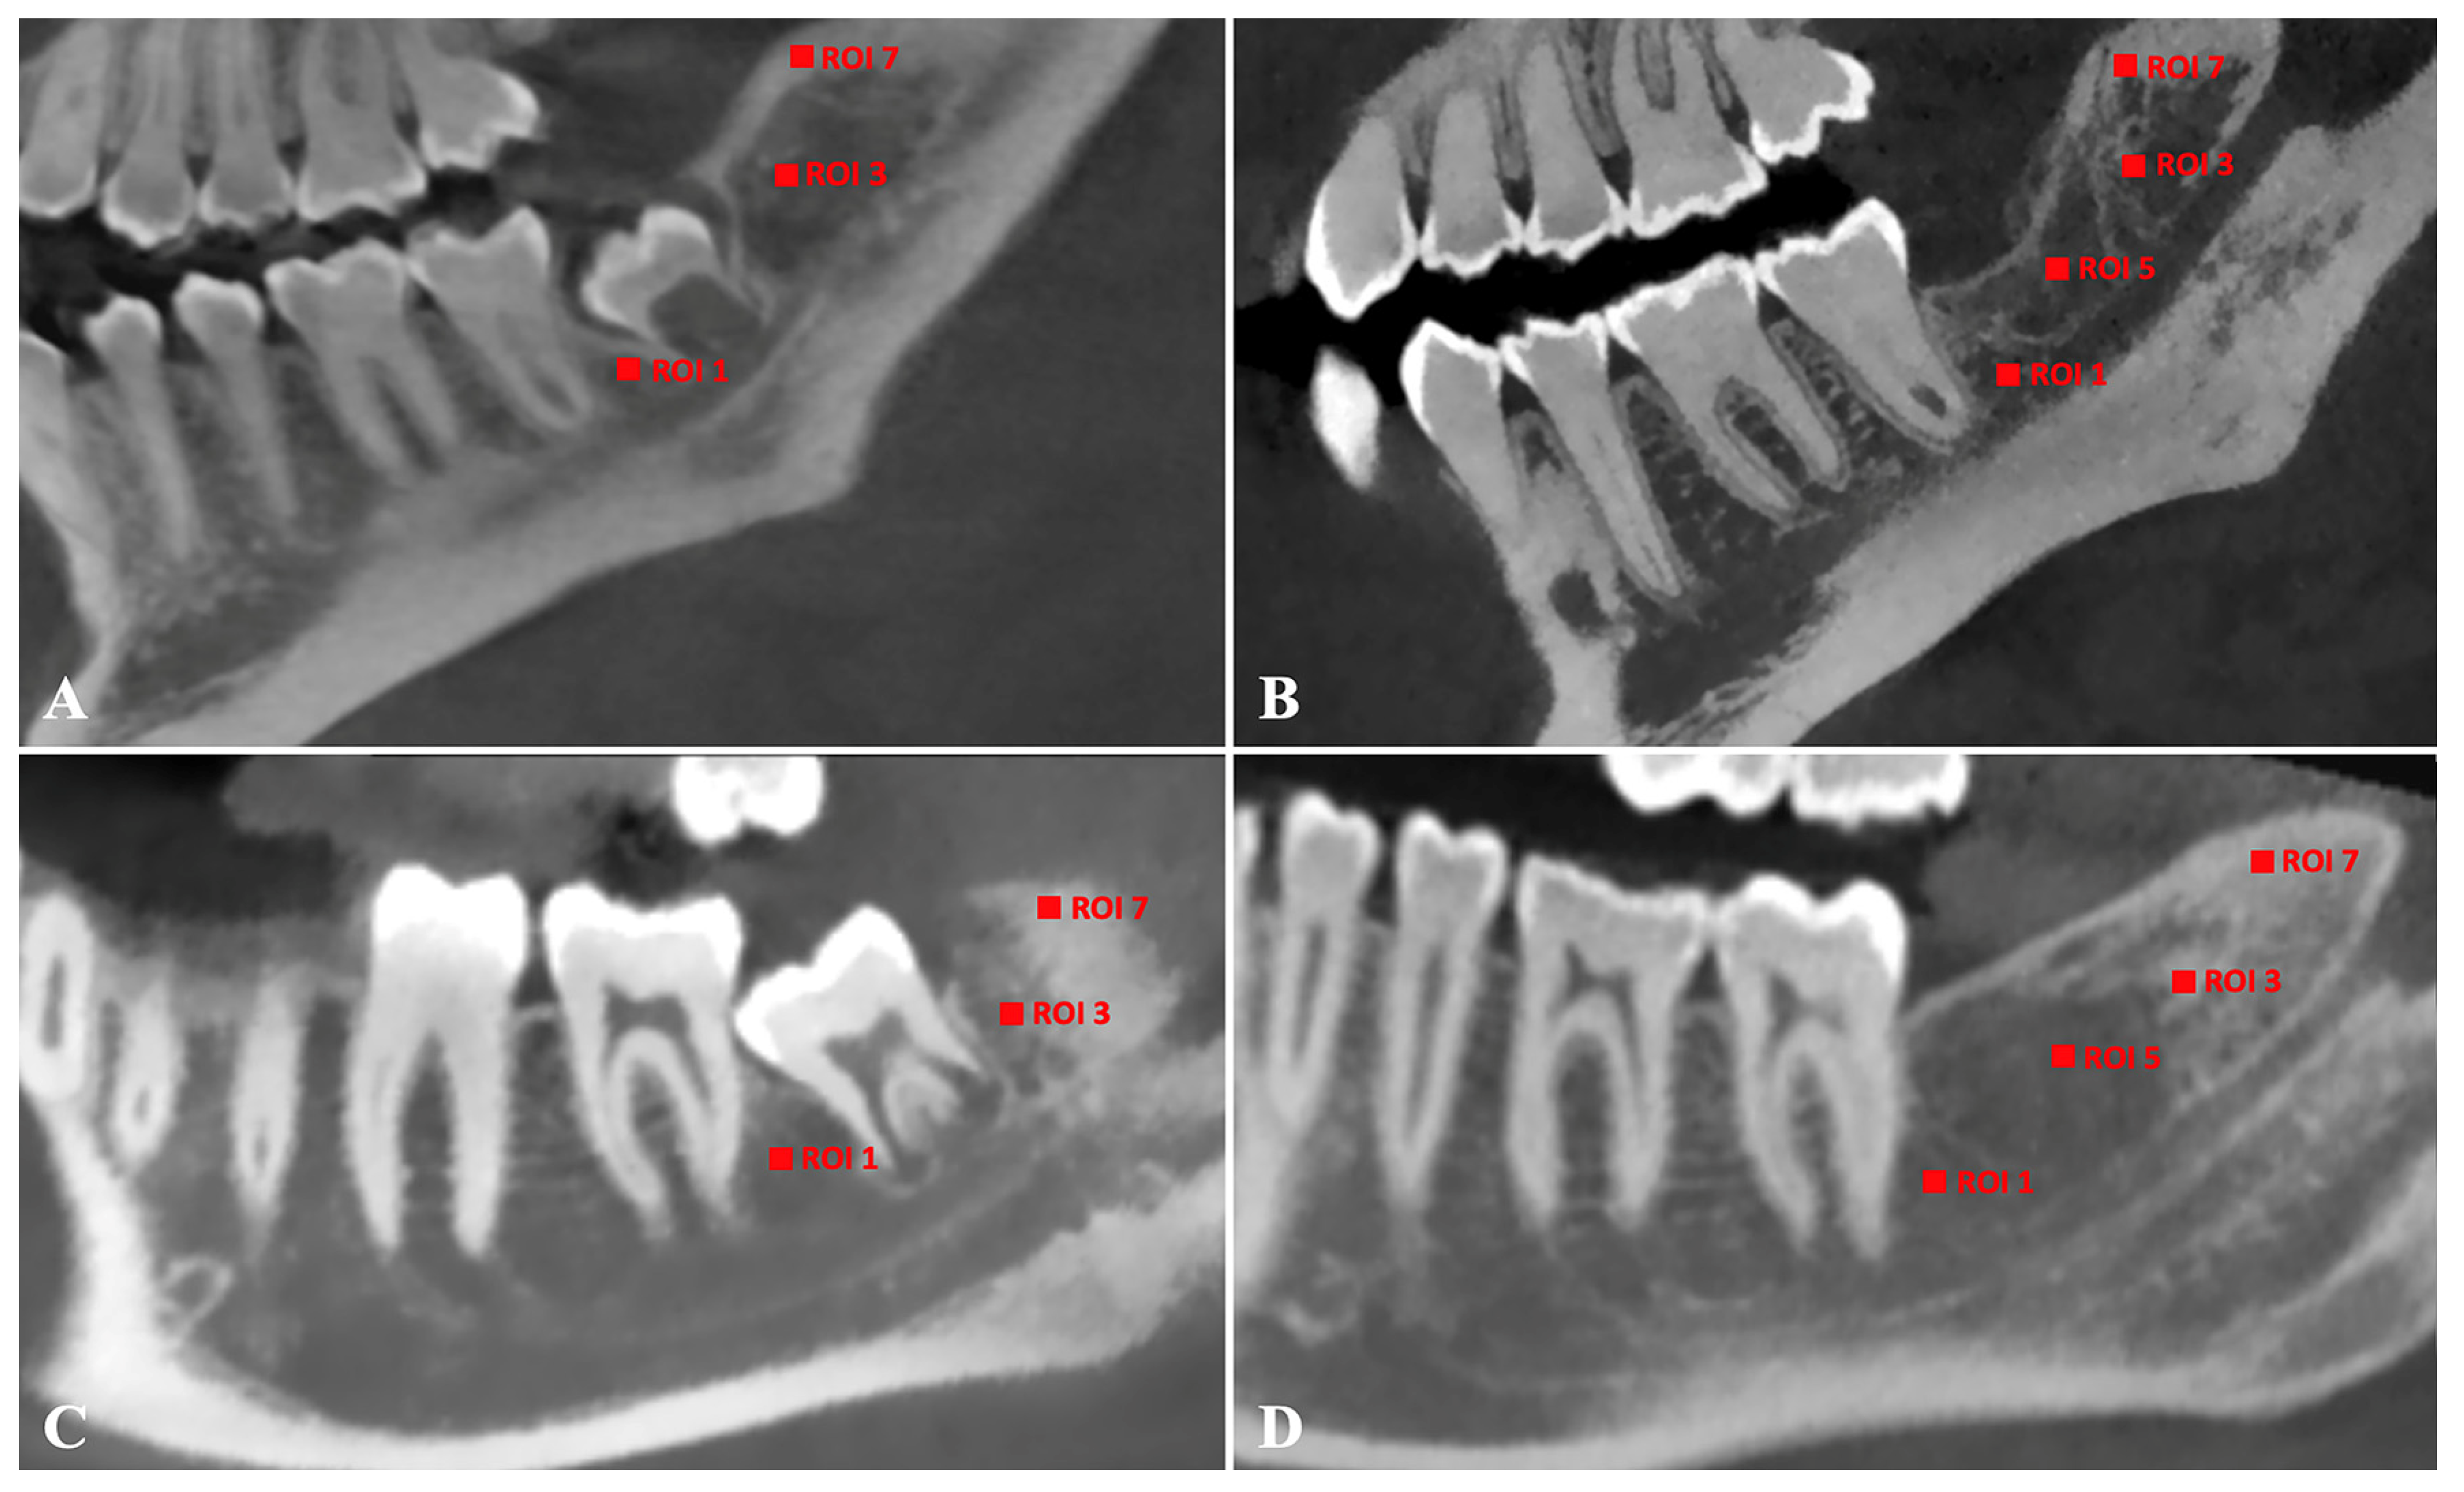

| ROI-1 | 4 | 309.36 ± 211.21 (160.05–612.56) | 4 | 467.73 ± 194.53 (244.12–717.25) | 4 | 288.43 ± 65.90 (207.24–349.47) | 4 | 338.86 ± 135.68 (183.15–514.28) |

| ROI-2 | 5 | 265.03 ± 98.28 (157.67–418.77) | 5 | 441.77 ± 125.81 (337.57–640.03) | 4 | 243.32 ± 74.76 (176.18–310.62) | 4 | 307.85 ± 86.16 (206.24–417.03) |

| ROI-3 | 4 | 346.04 ± 248.57 (180.52–705.95) | 4 | 684.75 ± 120.65 (529.37–793.10) | 4 | 314.76 ± 75.25 (206.29–370.83) | 4 | 347,70 ± 46.64 (337.73–392.61) |

| ROI-4 | 5 | 337.49 ± 214.65 (161.22–680.85) | 5 | 605.44 ± 177.59 (349.71–772.23) | 4 | 303.15 ± 102,20 (206.62–398.88) | 4 | 426.58 ± 169.28 (237.00–615.32) |

| ROI-5 | - | NA | 4 | 214.60 ± 59.28 (165.73–289.16) | - | NA | 4 | 209.99 ± 36.88 (171.53–259.89) |

| ROI-6 | - | NA | 5 | 227.20 ± 111.81 (116.41–367.03) | - | NA | 4 | 262.74 ± 105.87 (160.98–380.42) |

| ROI-7 | 4 | 1580.87 ± 400.69 (1304.33–2162.02) | 4 | 1672.69 ± 197.85 (1498.86–1852.58) | 4 | 1373.90 ± 260.35 (990.65–1552.27) | 4 | 1360.09 ± 164.62 (1145.43–1512.30) |

| ROI-8 | 5 | 1659.02 ± 523.16 (1430.10–2.524.80) | 5 | 1703.78 ± 140.55 (1458.11–1797.58) | 4 | 1336.22 ± 88.68 (1267.89–1462.00) | 4 | 1434.86 ± 154.16 (1207.30–1549.45) |